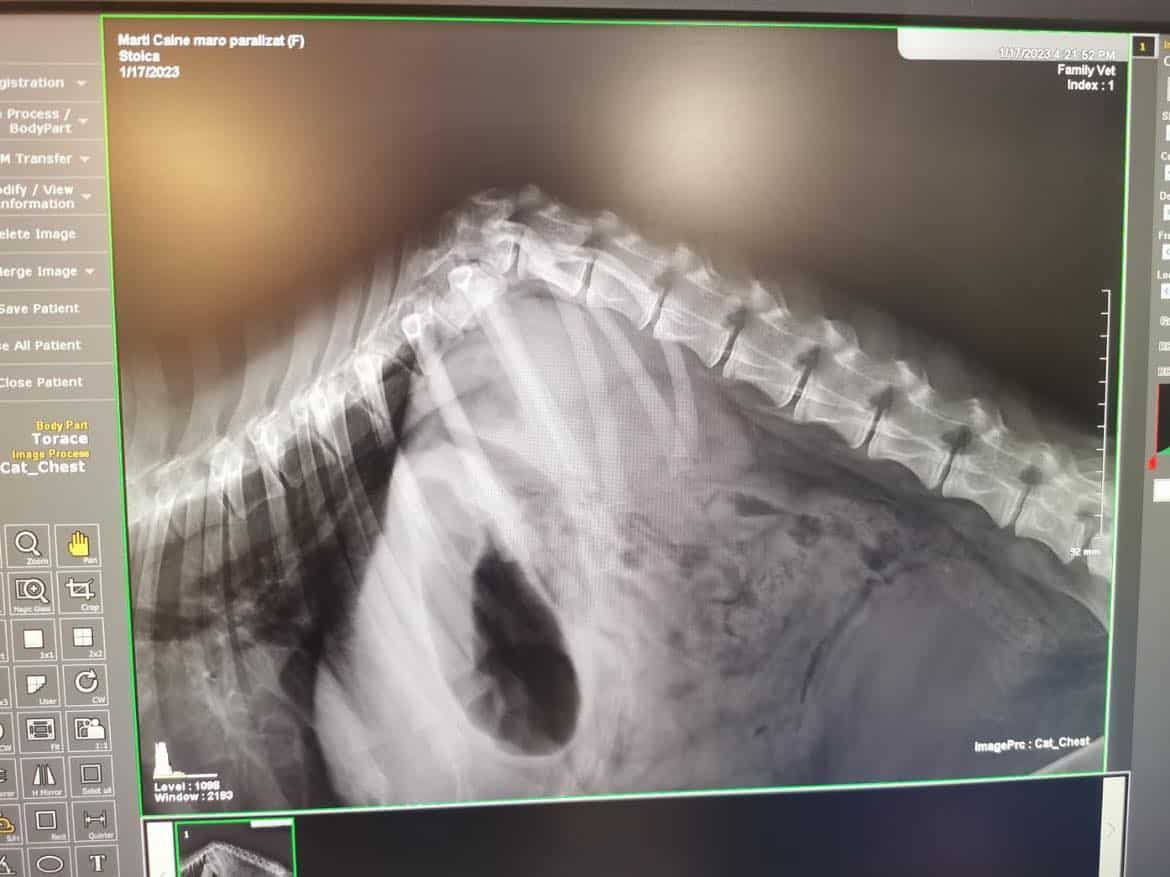

02/23 Zümra war in der Klinik und wurde geröngt, leider kann man in Rumänien für sie nicht mehr viel tun. Sie hat eine gebrochene Wirbelsäule. Wir versuchen nun erst einmal ein paar Übungen vor Ort und müssen schauen, ob sich etwas verbessert.

01/23 Wurde vom Auto angefahren und es wird in der Klinik geklärt, wie schwer die Verletzungen sind. Wir würden uns über Spenden und Paten freuen, um die Tierarztkosten stemmen zu können. Kontakt und Paypal (Geld an Freunde, sonst fallen gebühren an) Info@prodogromania.de